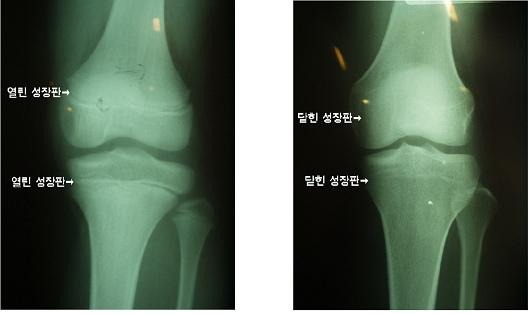

아이의 키의 성장이 걱정된다면 이러한 성장판을 촬영하여 성장을 예측해 볼 수 있습니다.

자세한 계산방법은 전문적인 포스팅에 추후 하도록 하겠습니다.